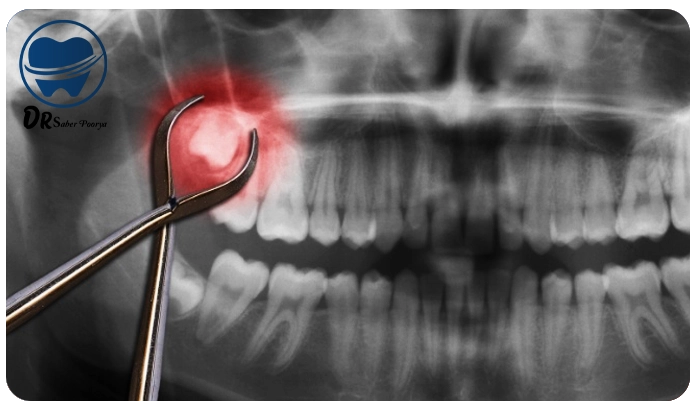

چرا باید دندان عقل را بکشیم؟

دندان عقل، آخرین دندانی است که در انتهای فک رشد میکند و اغلب بین ۱۷ تا ۲۵ سالگی ظاهر میشود. در بیشتر موارد، فضای کافی برای رشد درست این دندان وجود ندارد و همین مسئله باعث مشکلاتی مانند:- درد و فشار در فک

آیا کشیدن دندان عقل درد دارد؟

انواع دندان عقل و روشهای کشیدن

- دندان عقل نهفته کامل: کاملاً زیر لثه یا استخوان فک است و نیاز به جراحی دارد. این مورد معمولاً توسط متخصص جراحی فک انجام میشود.